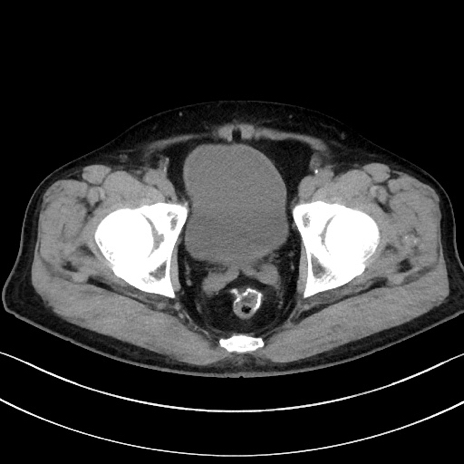

症例15(横断像)

【症例】70歳代男性

【主訴】腹痛

【現病歴】今朝から腹痛あり。全体的に痛い。特に左上の方。排ガスが今日はない。冷や汗が出る。

【既往歴】直腸癌術後

【身体所見】左側腹部〜上腹部に圧痛あり。腹膜刺激症状明らかなではない。軽度反跳痛。左下腹部に術後瘢痕あり。

【データ】WBC 7700、CRP 0.02